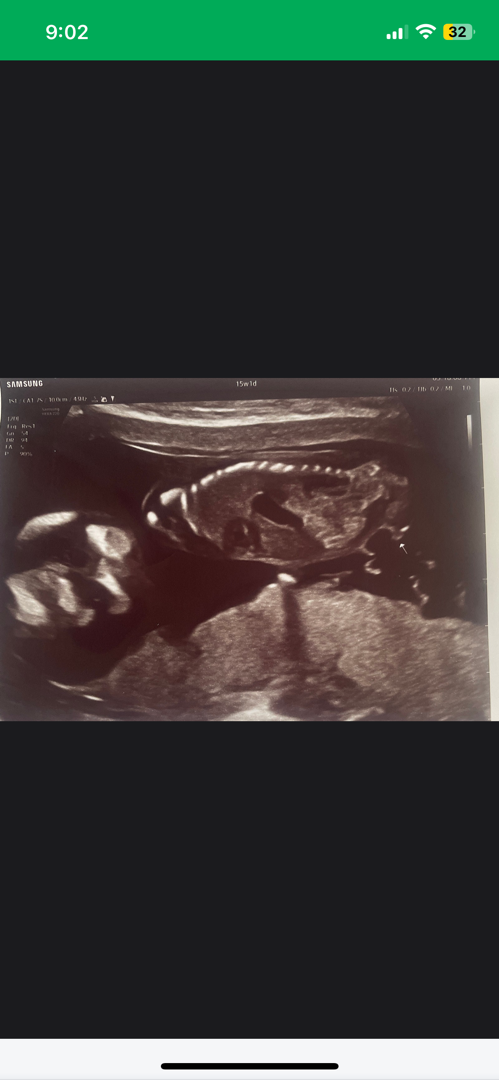

15주차 성별 나중에 반전 있을까요??

삼각점인가요… 곧휴인가요…ㅠㅠㅠㅋㅋㅋ둘째인데 아둘맘인지.. 반전이 잇을찌… ㅠㅠㅠㅋㅋㅋ저 튀어나온ㄱㅔ 쏙 들어갈 확률이 있을까요??